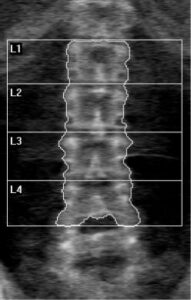

DXA可發出二種不同強度的X光掃描身體,我們選擇正面腰椎掃描、與髖骨包含全髖骨及股骨頸掃描模式,以國際臨床骨密學會規定之擺位與電腦做分析。掃描所需時間約為5-10分鐘。

使用世界衛生組織(WHO)的骨質密度分類標準「T評分(T-score)*」,T負數值越大,表示骨密度越低,骨折風險也越高。(T值≧–1)正常或骨質健康、(–1>T值>–2.5)骨質流失、(–2.5≧T值)骨鬆且值越大骨鬆越嚴重。

健康骨質密度

骨質疏鬆

57歲女性,已停經

身高164cm、體重66kg、BMI 22.63 kg/m2

T值–0.7(正常)

56歲女性,已停經

身高158cm、體重68kg、BMI 27.03 kg/m2

T值–3.4(骨質疏鬆)